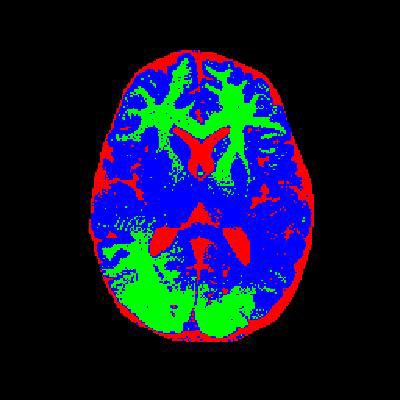

4. 实验结果与分析

通过实验验证,改进后的算法在噪声较多的图像上表现出了更好的鲁棒性和分割效果。以下是部分实验结果:

- 分割结果:如图3所示,改进后的算法能够有效地对目标区域进行分割,同时抑制噪声的干扰。